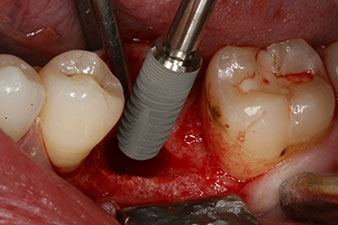

Fig. 3 : Après préparation à l'aide du moteur d’implantologie Implantmed, un implant (4 mm de diamètre, 12 mm de long) a été vissé à l’aide du moteur avec un couple de 43 Ncm.

L’implant a été posé comme prévu après élimination complète du tissu de granulation (blueSky, bredent).

Le couple utilisé pour la pose guidée était de 43 Ncm.

En outre, après avoir vissé une tige de mesure (SmartPeg) spécialement conçue pour l'implant, la valeur ISQ a été mesurée à l’aide de la sonde du module W&H Osstell ISQ.

déficit osseux péri-implantaire

Fig. 5 : Le déficit osseux péri-implantaire doit être compensé par des fragments osseux autogènes afin de restaurer le contour des tissus péri-implantaires.

Ce module est fourni en option avec l’Implantmed de W&H et est fixé au moteur d’implantologie (cf. Fig. 11). La valeur ISQ adimensionnelle mesurée immédiatement après l’insertion était de 64 dans l’axe oro-vestibulaire et de 68 dans l’axe mésio-distal (valeur maximale = 100).

Ces valeurs auraient pu indiquer une cicatrisation ouverte, voire une restauration immédiate. Étant donné le volume osseux crestal insuffisant au niveau de l’implant, une augmentation osseuse a été pratiquée localement à l’aide des fragments osseux recueillis lors de la préparation du lit implantaire, et des points de suture effectués pour éviter le contact de la salive.